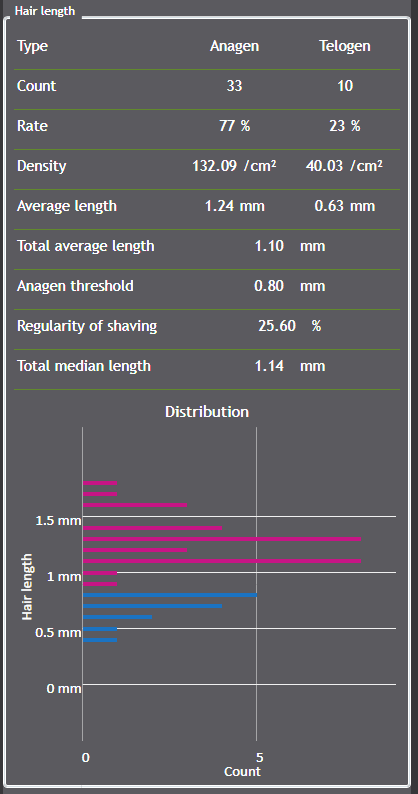

100% automated hair analysis using AI segmentation

Thanks to advanced AI-powered segmentation algorithms, the C-Cube now enables fully automated detection of hair fibers in the image.

Each hair is individually identified, which allows for:

-

automatic diameter calculation,

-

measuring hair length and regrowth,

-

quantification of density.

This automation reduces analysis time, minimizes operator variability, and ensures optimal reproducibility in longitudinal studies.